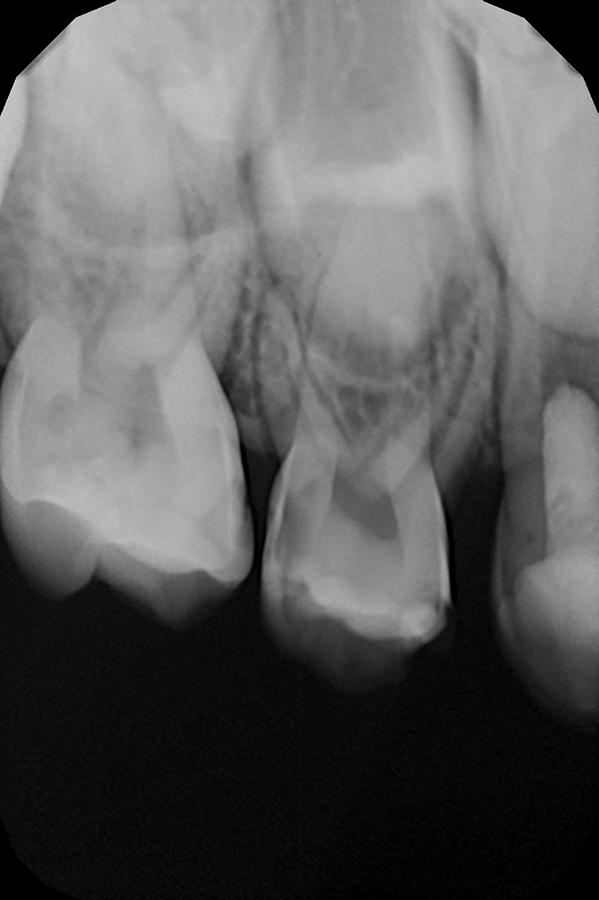

Диагностика и лечение скрытого кариеса на постоянном зубе у семилетнего ребёнка